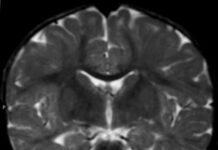

Promising treatment for Alexander disease

Alexander disease refers to a progressive disorder of cerebral white matter, commonly detected in infants and children. Its prevalence is unknown; however, approximately 500...